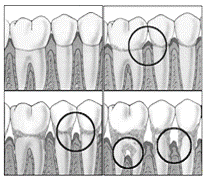

Рис.5.- Стадии развития воспалительных процессов в пародонте.

Табл. 2. - Признаки воспаления.

Стадии Изменения

Первичное повреждение

Раннее повреждение

Развившееся повреждение

Тяжелое повреждение

Функциональные изменения

Воспаление сосудов; разрушение коллагена

Воспаление сосудов; разрушение коллагена; инфильтрация лимфоцитов в соединительные ткани десны

Накопление воспаленных клеток между сосудами и коллагеном; потери коллагена в поврежденной области

Проникновение эпителия в соединительную ткань; воспаление альвеолярной кости

Изменение оптических свойств

Увеличение коэффициента поглощения

Основываясь на рассмотренных признаках воспаления тканей пародонта можно заметить, что по мере развития воспалительного процесса происходит изменение концентрации веществ-хромофоров, что обуславливает изменение оптических свойств тканей. Следовательно, существует возможность применения оптических методов для диагностики мягких тканей в полости рта.